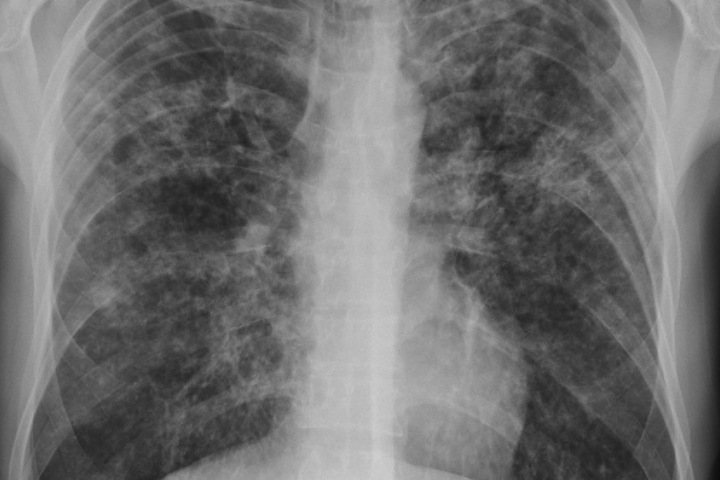

Четыре жителя Гурьевска с открытой формой туберкулеза уклонялись от лечения, подвергая опасности окружающих. Прокуратура направила в суд иск об их принудительной госпитализации.

Иск о принудительном лечении и госпитализации был подан Гурьевским межрайонным прокурором. Ведомство указывало, что без госпитализации эти люди могут заразить своих знакомых туберкулезом. Суд согласился с требованиями и удовлетворил исковые заявления, сообщает прокуратура Кемеровской области. Трое больных уже госпитализированы, одно заявление пока находится на исполнении у приставов.

По данным администрации Кемеровской области на 2018 года Кузбасс занимает второе место в СФО по количеству больных туберкулезом среди населения региона.